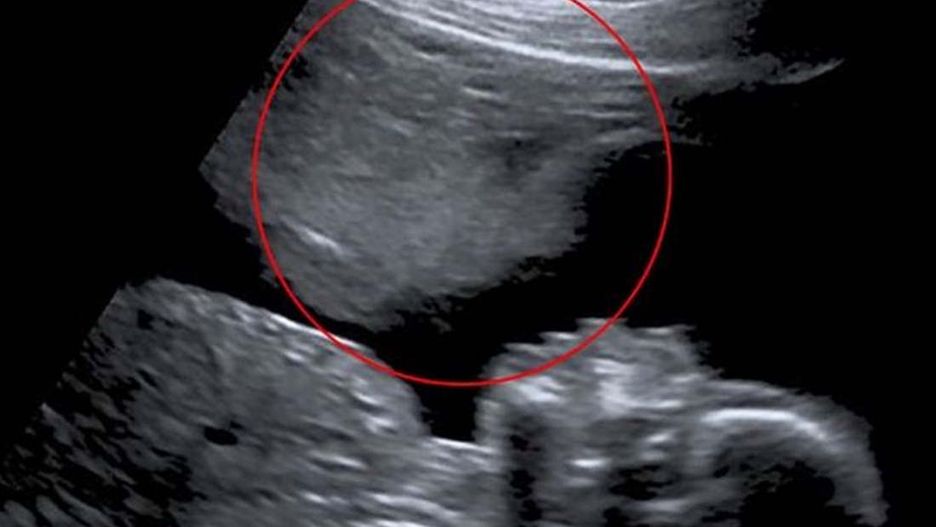

W 20. tygodniu ciąży wykonano badanie, które okazało się przełomowe. Stacey otrzymała zdjęcie USG, na którym zauważyła coś niezwykłego - kontur przypominający twarz. Dla Stacey był to znak, że nie jest sama, a ktoś "pomagał" jej przetrwać te trudne chwile.

"Myślę, że to mógł być ktoś lub coś, co nad nami czuwało" - powiedziała.